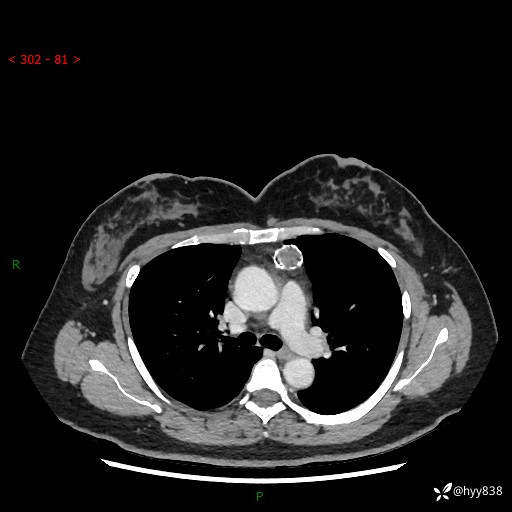

中年女性,检查发现纵隔占位3月余。圆圆的肿物,周围环绕一圈钙化---结果公布~

主诉:检查发现纵隔占位3月余。

现病史:患者于3月前体检行胸部CT检查发现纵隔占位,患者平素无明显咳嗽咳痰,无心慌、胸闷、胸痛、呼吸困难、低热、盗汗,无头痛、头晕,无腹痛、腹胀等不适。现患者欲求进一步治疗,遂来我院就诊,以“纵隔占位”收入我科。 患者自起病以来,精神可,睡眠可,饮食可,大小便正常,体重无明显改变。

胸部CT平扫+增强